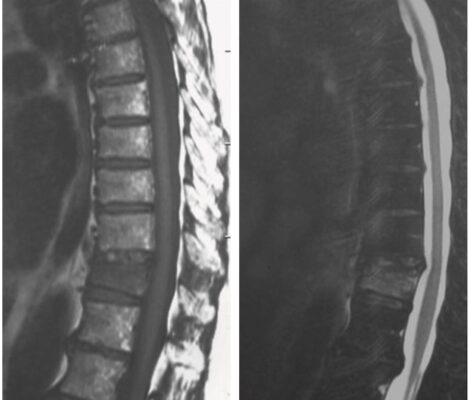

- X quang ngực thẳng và nghiêng là xét nghiệm có giá trị chẩn đoán, phát hiện đốt sống bị giảm chiều cao, thường có dạng hình nêm, với chiều cao phía trước nhỏ hơn chiều cao đốt sống sau. Trong bệnh loãng xương, X quang cũng có thể phát hiện đốt sống bị biến dạng lõm hai mặt.

- Chụp CT scan hoặc cộng hưởng từ (MRI) được chỉ định khi cần làm rõ thêm chi tiết, nhất là khi nguyên nhân do chấn thương nặng, đau ở vị trí bất thường (ví dụ ở đốt sống ngực cao), có dấu hiệu tổn thương thần kinh hoặc nghi ngờ bệnh lý khác.